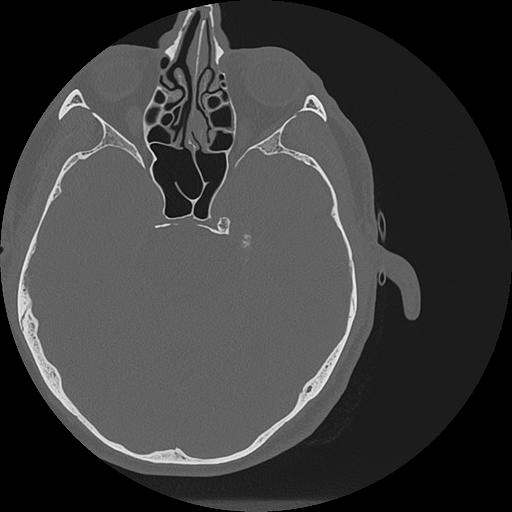

7 HUESO,,Vol,0.5,HUESO,,